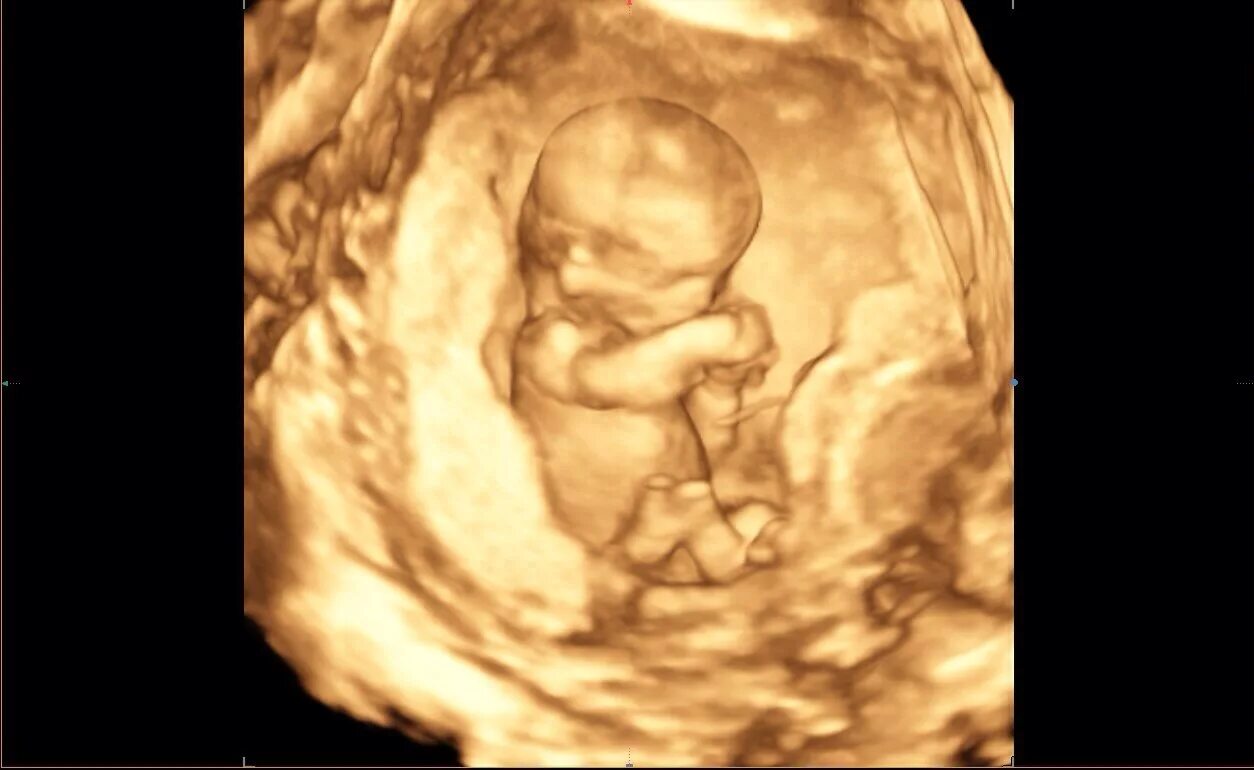

12 недель и два дня